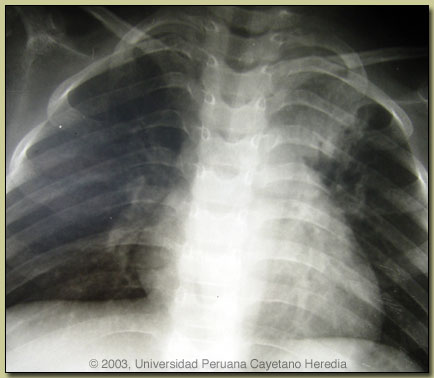

| Diagnosis: Pott's disease; presumed tuberculous meningitis; presumed pulmonary tuberculosis. |

Discussion: Chest X-ray (see Image at right) shows apical lesions consistent with pulmonary tuberculosis. Results of a gastric aspirate and urine for AFB are pending. Serum ADA (adenosine deaminase), used in many countries as an indicator of possible TB infection, was 30 (upper limit of normal 21).